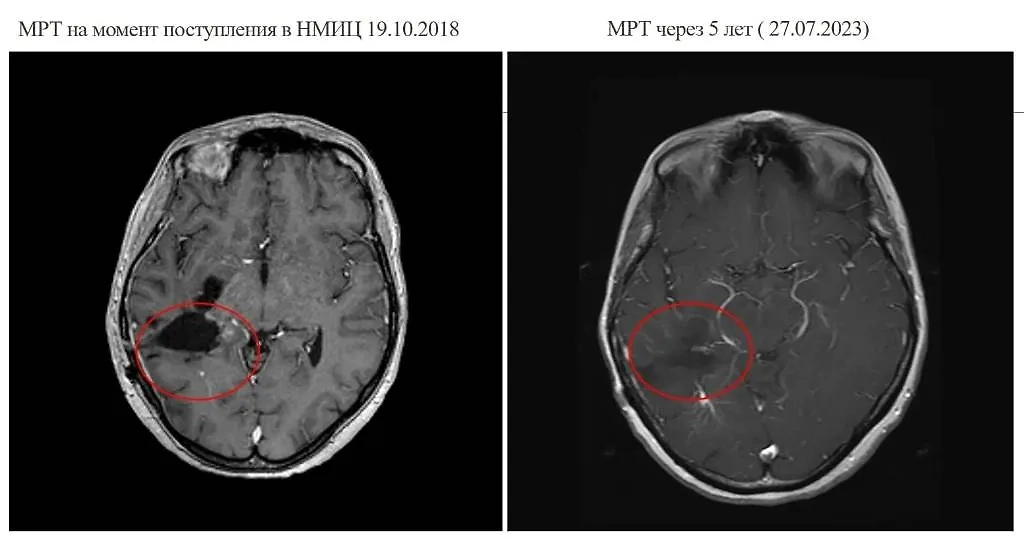

МРТ на момент поступления сибирячки с опухолью в больницу и через пять лет после лечения. Фото © VK / НМИЦ им. ак. Е.Н. Мешалкина Минздрава России

"Жительница Кемеровской области, ведущая активный образ жизни и страстно увлечённая спортивным туризмом, узнала свой диагноз пять лет назад, в июне 2018 года. У неё обнаружили глиобластому — наиболее злокачественную опухоль мозга, для которой характерны стремительный диффузный рост и глубокое внедрение в здоровые окружающие ткани мозга", — пояснили там.

По словам Самойловой, онкологи прибегли к переливанию тромбомассы, а также антибактериальной и противогрибковой терапии. В итоге состояние женщины удалось стабилизировать, её выписали. При этом в течение года показатели крови ещё восстанавливались до нормы, поэтому пациентка не смогла по показаниям получать дальнейшую химиотерапию. И, несмотря на это, по прошествии пяти лет она стала одним из пяти счастливчиков, которые по общемировой статистике выживают с глиобластомой.

Теперь кемеровчанка живёт полной жизнью и ощущает себя полностью здоровой. Она ходит в походы, сплавляется на байдарках и радуется каждому дню. Новых очагов опухоли в головном мозге женщины врачи не зафиксировали.